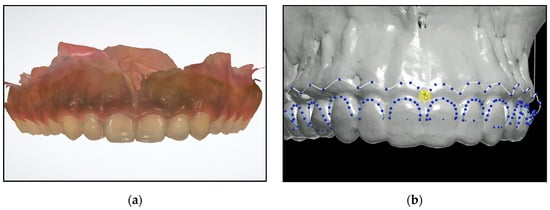

An intraoral scan (TRIOS; 3Shape) was acquired to aid in fabricating a surgical guide (Figure 3a). Digital Imaging and Communications in Medicine (DICOM) files were converted to Standard Tessellation Language (STL) format and then superimposed with STL files acquired from the intraoral scan using coDiagnostiX 9.7 software (Dental Wings INC, Montreal, Canada). Then using the design software (3Shape Premium Dental System; 3Shape), the level of the cementoenamel junction was marked (Figure 3b) to guide the gingivectomy incision line, followed by a second line 3 mm apical to the cementoenamel junction line to guide the bone resection. The virtual design of the surgical guide was performed accordingly.

Figure 3.

(a) Intraoral scan of the maxillary jaw; (b) After superimposition of the CBCT and the intraoral scan, the cementoenamel junction and future bone level marked.